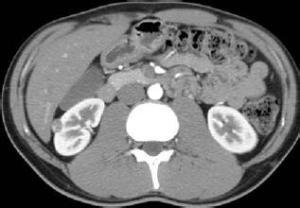

肝脏炎性假瘤(IPT)是非肝实质性细胞成分的炎性增生病变,是一种良性增生性瘤样结节。该病可能与创伤、感染及免疫、变态反应等因素有关。该病发病以儿童多见,患者多为单发病灶,部分为多发。[1]